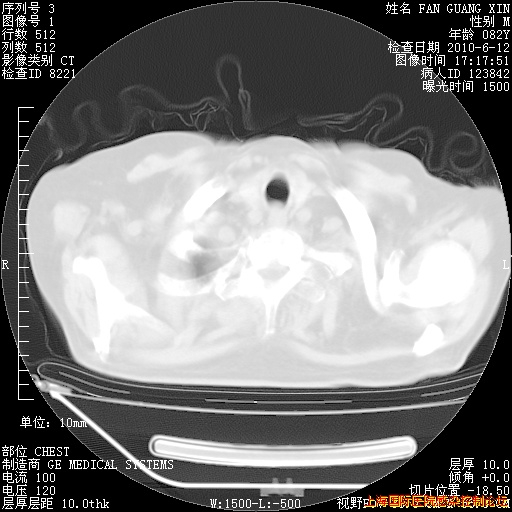

补发6月12日肺部CT肺窗

回复